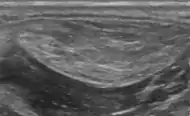

A physical exam is typically the easiest way to diagnose it. Rarely, a tissue biopsy or imaging may be required. The imaging modality of choice is magnetic resonance imaging (MRI) because it has superior sensitivity of distinguishing it from liposarcoma as well as mapping the surrounding anatomy.[22]